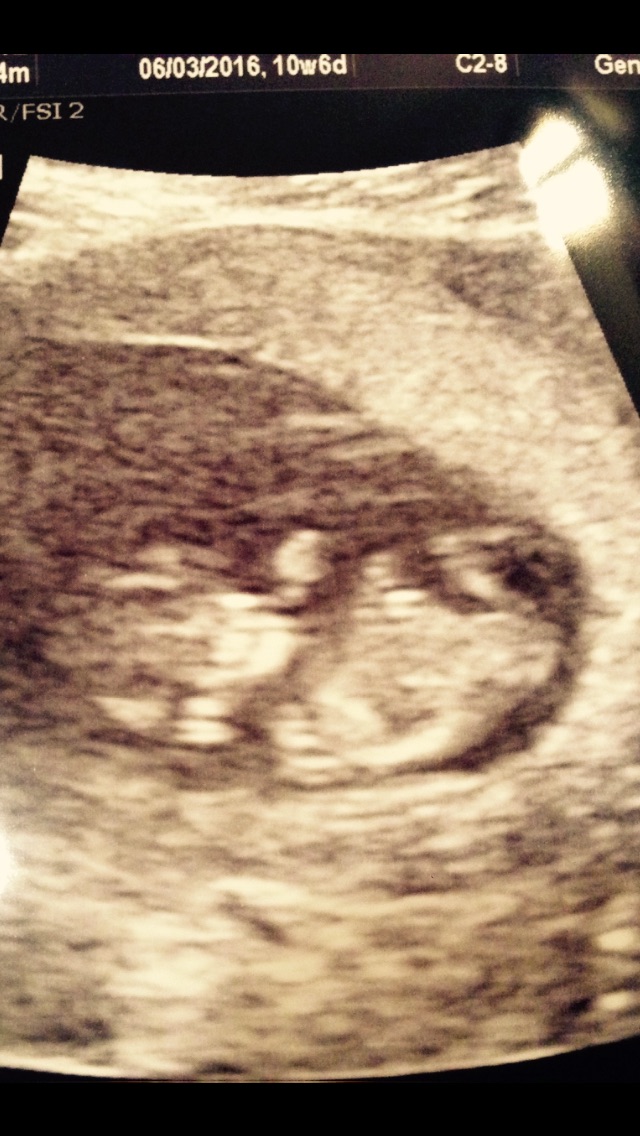

Today was my first ultrasound! I feel so relieved now that everything went well. I'm measuring as I should be. I'm 10w1d. The baby's heart beat was 163! I'm so in love! I can't stop looking at my pictures. I also got to see 3D and it was amazing. Feels so much more real now! I'll have to wait I guess to post my pic